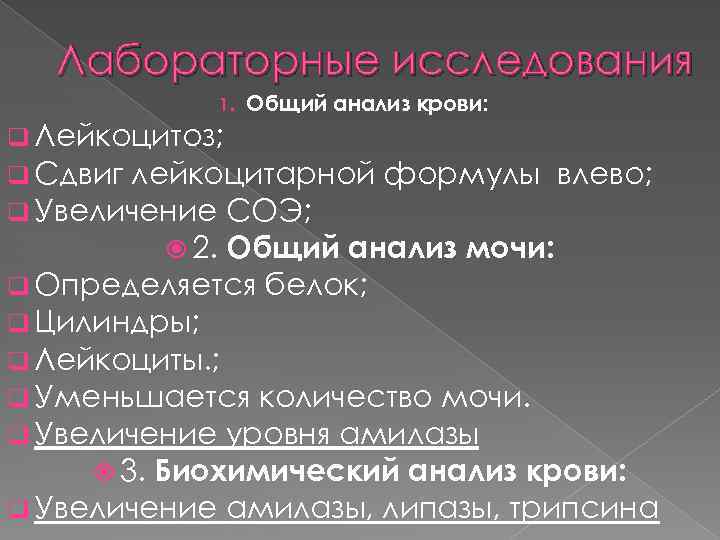

Лабораторные исследования 1. Общий анализ крови: q Лейкоцитоз; q Сдвиг лейкоцитарной формулы влево; q Увеличение СОЭ; 2. Общий анализ мочи: q Определяется белок; q Цилиндры; q Лейкоциты. ; q Уменьшается количество мочи. q Увеличение уровня амилазы 3. Биохимический анализ крови: q Увеличение амилазы, липазы, трипсина

Лабораторные исследования 1. Общий анализ крови: q Лейкоцитоз; q Сдвиг лейкоцитарной формулы влево; q Увеличение СОЭ; 2. Общий анализ мочи: q Определяется белок; q Цилиндры; q Лейкоциты. ; q Уменьшается количество мочи. q Увеличение уровня амилазы 3. Биохимический анализ крови: q Увеличение амилазы, липазы, трипсина